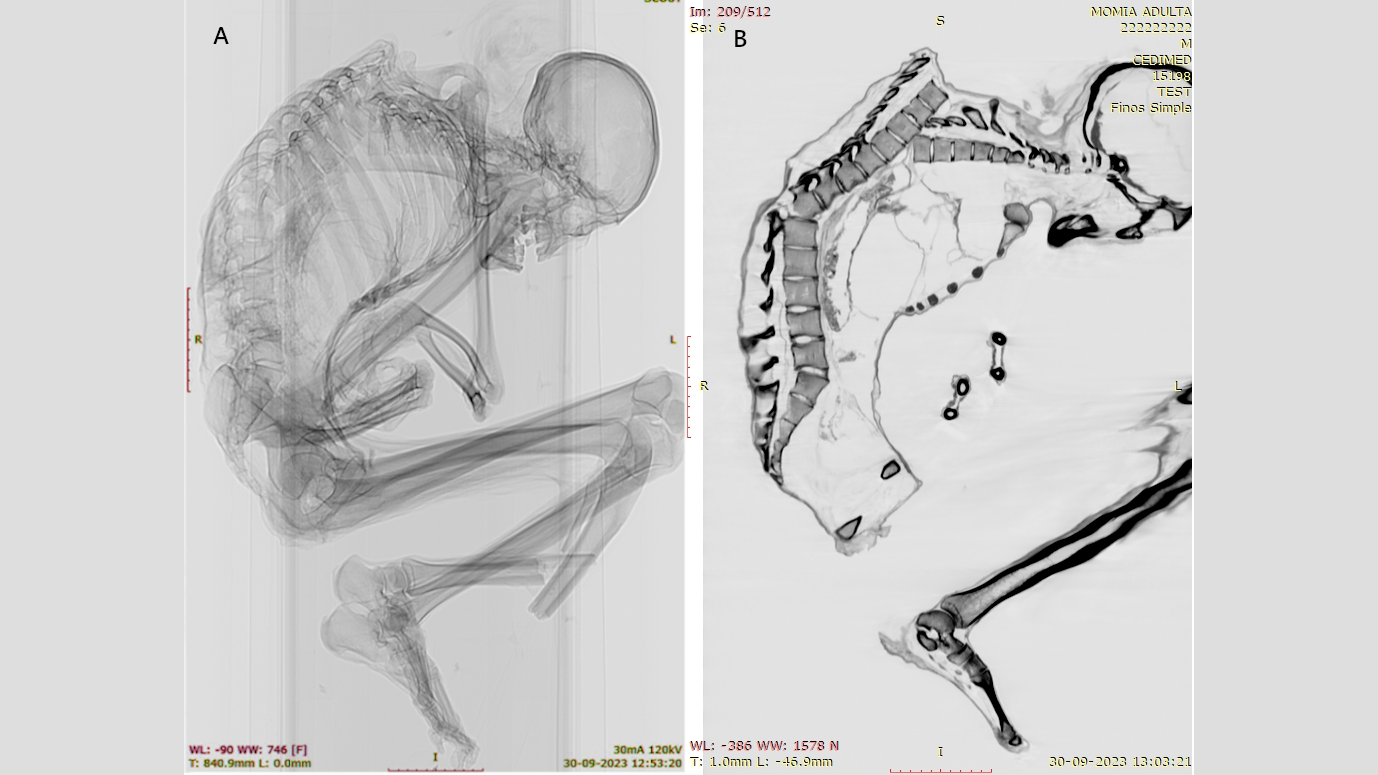

In a study published Dec. 15 in the International Journal of Osteoarchaeology, Catalina Morales and Francisco Garrido, archaeologists at the National Museum of Natural History in Santiago, Chile, used CT scans and X-ray imaging to reveal intricate details of the extensive trauma that probably resulted in the man's death.

Multiple unhealed fractures were evident on the man's upper spine. He also had rib, shoulder blade and collarbone fractures, which suggest "a blunt force impact over a wide area" of his upper back, revealing his "upper left thorax bore the brunt of the impact," Morales and Garrido wrote in the study. The impact displaced several of his vertebrae and collapsed his rib cage.

Additionally, the researchers identified a fracture in a vertebra near the base of his spine, likely the result of the initial upper-back injury. The upper- and lower-spine injuries are both "typically associated with severe spinal cord damage and high mortality," the researchers wrote.

But there were no injuries found to the man's skull, neck or arms, which indicates that the impact occurred when the man was in a head-down body position. He may have been actively mining or perhaps attempting to protect his head with his arms when he was struck by a heavy object falling from above. This type of injury is seen in the bodies of people involved in earthquakes and in occupational accidents in forestry, construction and mining, the researchers wrote.